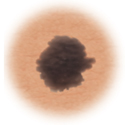

Moles (nevi)

Small skin marks caused by pigment-producing cells in the skin. Moles can be flat or raised, smooth or rough, and some contain hair. Most moles are dark brown or black, but some are skin-colored or yellowish. Moles can change over time and often respond to hormonal changes.

Most moles are benign and no treatment is needed. Some benign moles may develop into skin cancer (melanoma). See below for signs.

Normal mole.